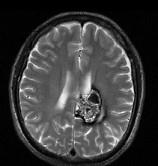

问题 男,59岁,反复头晕头痛半年余,重体力活时头痛明显,请根据所提供图像,选择最可能的诊断()

选项 A.(左顶)海绵状血管瘤 B.(左顶)室管膜瘤 C.(左侧脑室)胶质瘤 D.(左侧脑室)脉络膜乳头状瘤 E.(左顶)动静脉血管畸形

答案 A